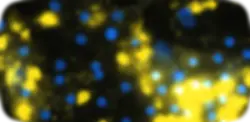

Cholestasis

Bile Canaliculi Loss

Hoechst (Nuclei) Phalloidin (Actin)

Lysosomal Disruption

Lipofuscin Buildup

Hoechst (Nuclei) Lysosomal (Autofluorescence)

Mitochondria

Fission and Fusion

Hoechst (Nuclei) Mitotracker